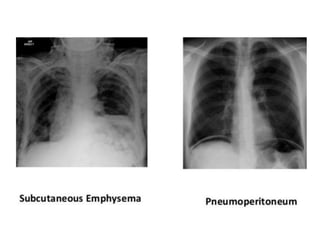

This document provides an overview of interpreting chest x-rays and identifies several key factors. It discusses the importance of inspiration, penetration, and rotation in obtaining a technically quality radiograph. It also outlines different views of chest x-rays including PA, AP, and lateral views. Finally, it identifies several anatomical structures that should be evaluated when interpreting a chest x-ray such as the lungs, heart, diaphragm, bones, and soft tissues.